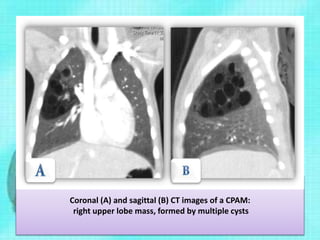

Coronal (A) and sagittal (B) CT images of a CPAM:

right upper lobe mass, formed by multiple cysts

CCAM • CT helpsin confirming the diagnosis, characterization of the lesion, and to document the involved lobe or segment • Intravenous contrast media must be used to define the presence of any systemic arterial vessels supplying the lesion • CT also helps to diagnose other associated congenital malformations

Coronal (A) andsagittal (B) CT images of a CPAM: right upper lobe mass, formed by multiple cysts